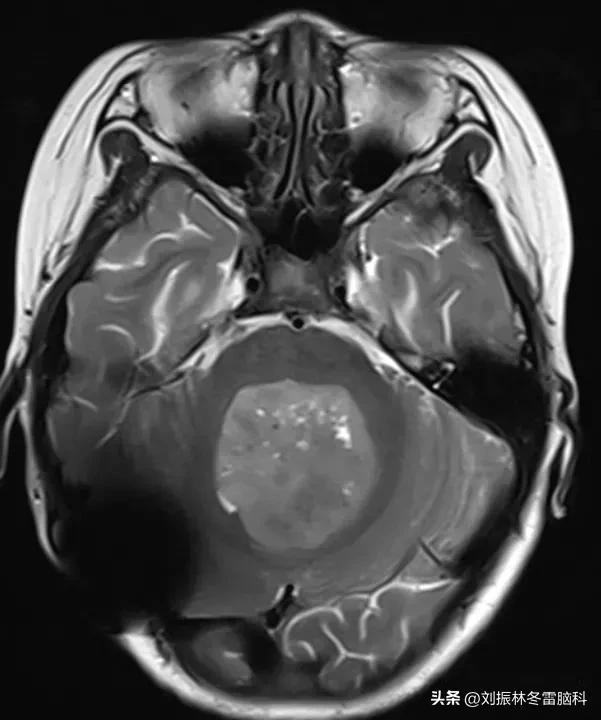

核磁图片

小儿髓母细胞瘤的发生机制不明确,目前认为肿瘤细胞起源于小脑神经元祖细胞,其发生基因突变后无限制的增殖,形成髓母细胞瘤。髓母细胞瘤是一种恶性度较高的肿瘤,当肿瘤被发现时,往往肿瘤已经长得很大。核磁共振检查是筛查小儿肿瘤的主要方法,因CT检查对儿童有放射线辐射,因此儿童多采用核磁共振检查。